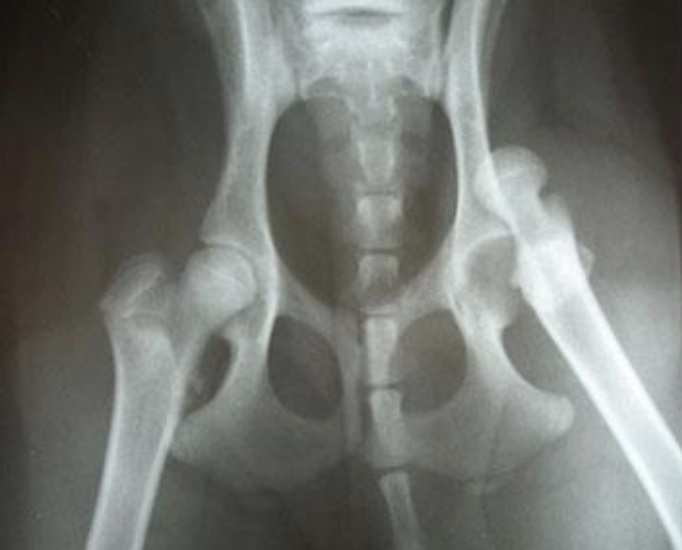

gait disorder: coxofemoral luxation

results of extreme trauma (hbc) or extreme ABduction of hip joint; limb appears shorter from behind; thigh adducted, stifle rotated outward, tarsus rotated inward